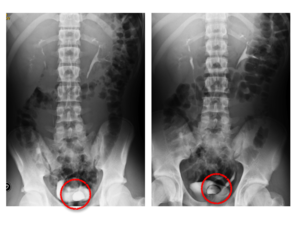

Paciente de 17 años, sin antecedentes de interés, que se envía a Nefrología por alteraciones de la analítica urinaria (hematuria y proteinuria de 1 + por tirita). Únicamente refería haber tenido semanas antes un episodio de disuria, dificultad para iniciar la micción y tenesmo, todo lo cual mejoró con un antibiótico. En la radiografía de abdomen y en la ecografía no se encontraron alteraciones. El urocultivo (tras el tratamiento indicado) fue negativo. Las urografías intravenosas demostraron el relleno de una cavidad intravesical, típica del denominado ureterocele (figura 1), dentro de la cavidad vesical. Se remitió a Urología para valoración quirúrgica.

El ureterocele consiste en una dilatación quística del uréter distal en su trayecto intravesical, que puede tener varios grados y se produce por una alteración en la embriogénesis por estenosis del orificio ureteral1-3.

En ocasiones se complica con hidronefrosis y anulación renal. En nuestro caso, el ureterocele es leve y solo se manifiesta por una infección urinaria. Queremos resaltar el papel de las urografías intravenosas en el estudio de las vías urinarias cuando el estudio básico con radiografía simple y ecografía es normal.

Figura 1. Dilatación quística del uréter distal izquierdo que se localiza dentro de la cavidad vesical